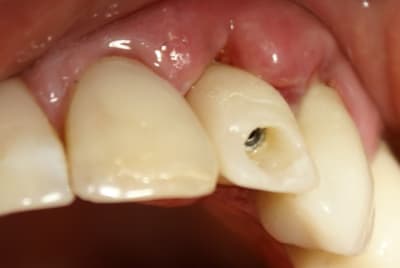

Dans ce cas là, c'était une implantation post extractionnelle immédiate et une mise en esthétique immediate.

Pour ceramik, l'implant est un Xive 3.8 dans le premier cas et un 3.4 dans le second (peut être un peu sous-dimentionné d'ailleurs).

Tout à fait d'accord growler et c'est d'ailleurs ce que l'on peut voir sur le cas suivant. Fracture radiculaire, aucune infection periradicualire. Extraction et implantation immediate. Espace existant entre l'implant et l'alvéole est comblé par du BioOss. Un logement sous gingival est formé en vestibulaire et palatin de facon à pouvoir recouvrir le tout par BioGide et un conjonctif enfoui.

L'implant est de 15mm mais l'alvéole était large et 50% environ de la surface implantaire n'était en contact qu'avec du BioOss. J'ai pour cela préféré enfouir.

Absolument pas. Fracture radiculaire comme précité.